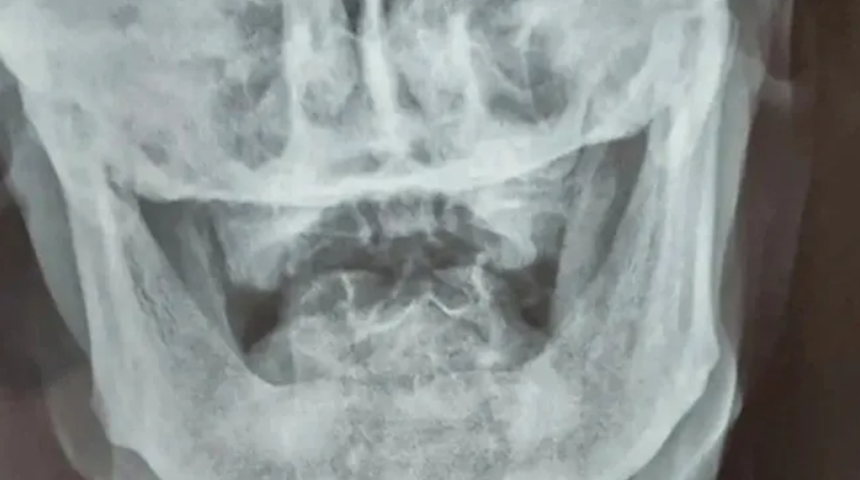

Çin'in Shandong kentindeki yerel bir hastanede son derece ilginç bir vaka yaşandı. 95 yaşındaki Zhao He isimli bir adamın başka bir hastalığından dolayı tedavi amacıyla geldiği hastanede çekilen röntgen görüntülerde boyun kısmına saplanan bir kurşun görüldü. Çin ordusuna henüz 15 yaşındayken katıldığını ve 1950’li yıllarda İkinci Dünya Savaşı cephelerinde yer aldığını dile getiren He, boynundaki kurşunun farkına olmadığını belirterek büyük bir şaşkınlık yaşadı. Damadı Wang, He'nin görevdeyken çok sayıda kurşuna maruz kaldığı ve boynundan vurulduğundan tamamen habersiz olduğu için tam olarak ne zaman vurulduğunu hatırlayamadığını söyledi.

Yaşı nedeniyle, ailesi ve tıp uzmanları, riskli bir cerrahi çıkarma girişiminde bulunmak yerine mermiyi olduğu yerde bırakmaya karar verdiler. Tıp uzmanlarına göre, kurşun He’nin boynuna saplandığı 80 yıl boyunca herhangi bir tıbbi duruma neden olmadı.